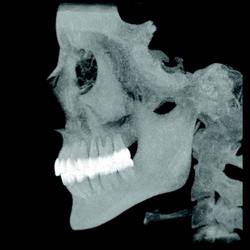

3-D software can shade images to differentiate varying densities of facial structures. Grayscale shading provides the ability to view the relationships of common internal anatomy. Traditional CT imaging renders an 8-bit grayscale (256 shades) or 12-bit grayscale (4,096 shades). Present-day scanners render images in 14-bit grayscale, providing 16,384 shades. Color coding the image by density further distinguishes anatomical structures, enabling the clinician to view pertinent anatomy while planning implant cases, such as nerves and nasal cavities, and mandibular and maxillary dimensions. Segmentation literally cuts the volume rendering, conceding top views, side views, and CT slices that produce unlimited axial, coronal and sagittal views. CBCT slices are as thin as 0.1 mm, compared to 1 mm for a conventional fan CT scan.